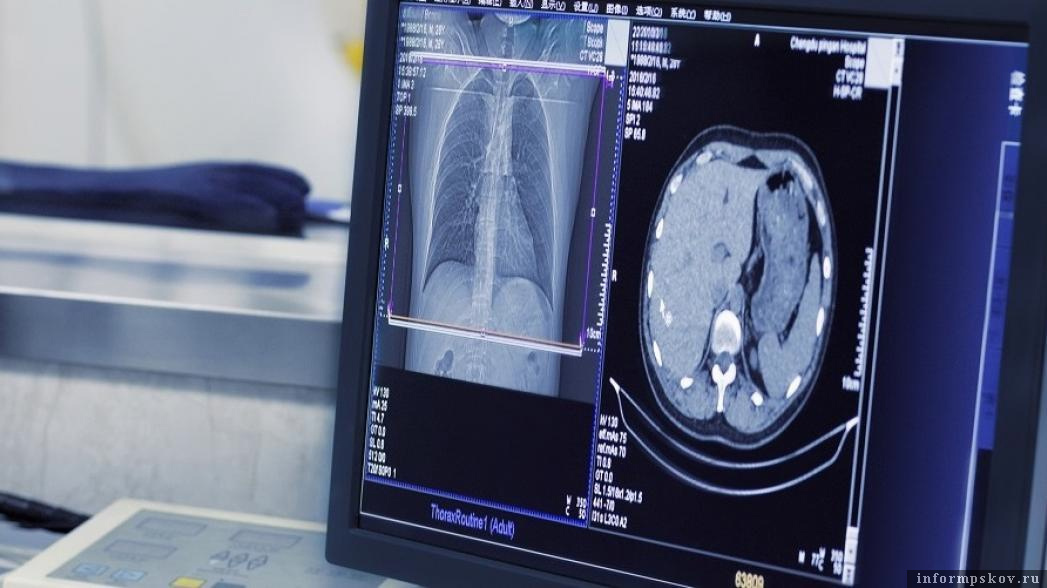

В работу Псковской областной инфекционной клинической больницы внедрён искусственный интеллект. ИИ помогает оценивать поражение лёгочной ткани, сообщили в комитете по здравоохранению Псковской области.

Данная методика позволяет врачам-рентгенологам учреждения исключить ошибки при оценке поражения лёгочной ткани во время проведения компьютерной томографии.

Искусственный интеллект может оперативно самостоятельно распознать патологию органов грудной клетки, определить процент поражения лёгочной ткани, что значительно облегчает работу врачей, добавили в комитете.